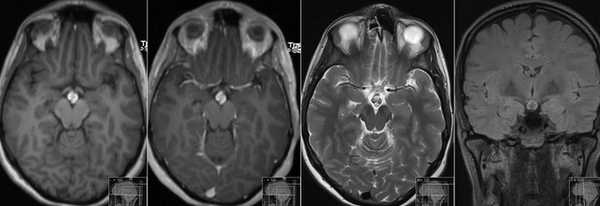

Макроаденома гипофиза на снимке МРТ

Выявление микроаденомы гипофиза с помощью МРТ: изображения в разных проекциях

Микроаденома гипофиза на снимках МРТ имеет ряд характерных признаков:

- неоднородная структура;

- округлая форма;

- очаг имеет гипоинтенсивный сигнал на Т1-взвешенных изображениях;

- выраженная граница, отделяющая образование от здоровых тканей;

- при наличии кровоизлияний и кист наблюдается усиление сигнала на Т2-взвешенных изображениях.

Для лучшей визуализации микроаденомы применяют динамическое контрастирование. Метод подразумевает использование короткого временного промежутка, когда велика разница сигналов между новообразованием и участками с нормальной структурой. На снимках МРТ с динамическим усилением аденома гипофиза в первой фазе исследования выглядит как гипоинтенсивный очаг на фоне умеренно контрастирующих здоровых тканей железы.